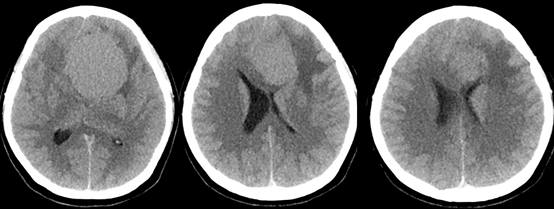

青年女性,因“左眼失明10个月,头痛3个月”就诊我院。

入院查体:神志清,精神可,言语流利,左侧瞳孔4mm>右侧瞳孔3.5mm,右侧对光反射存在,间接对光反射消失,左侧直接对光反射消失,间接对光反射存在,左眼失明,右侧鼻唇沟浅,四肢肌力及肌张力大致正常,双侧巴氏征未引出,颈软。

入院诊断:颅内占位病变(前颅窝底)脑膜瘤?;左眼失明;鼻炎

前颅窝底脑膜瘤常起源于前颅底筛骨筛板处的硬膜,瘤体多为双侧生长,少数为偏侧生长,女性稍多于男性。肿瘤可累及鸡冠和蝶骨平台的任何区域,是前颅窝肿瘤中最多见的一种。因为肿瘤位于前颅窝底,额叶在功能上属于“哑区”,患者就诊发现肿瘤时瘤体多已巨大。主要症状可有颅内压增高症状、视力减退、癫痫以及精神症状等。该患者主因“左眼失明10个月,头痛3个月”就诊。术中采用双额冠状开颅,左侧为主,由于肿瘤体积巨大,术中切除少许薄层额叶脑组织,边离断基底、边瘤内减压,分块切除肿瘤,最终探查肿瘤基底主要位于鸡冠、筛板、蝶骨平台、鞍结节、前床突处硬膜,术中见肿瘤供血主要来源于前颅窝底硬膜及大脑前动脉分支,术中仔细辨认供血动脉、过路血管,大脑前动脉及其分支保护完好,术中见视神经、视交叉受压明显,尤其是左侧视神经已缺血苍白,最终达Simpson II级切除。术者体会,该患者术前行多模态重建,可见瘤表数条粗大的静脉,术中切莫过早离断肿瘤的引流静脉,以防因引流不畅致瘤体肿胀出血;术前行多模态重建,利于鉴别供血动脉、过路血管,早期离断供血动脉更利于肿瘤切除;该类肿瘤基底一般较为广泛,不能盲目离断基底,尤其是近鞍结节处,可以于中线处离断基底,进入第一间隙后向两侧探查并保护视神经,待充分缩小瘤体看清楚毗邻的血管神经后再将其完全切除;术毕做好多层颅底重建以防脑脊液漏。另外,该患者术前左眼失明已达10个月,术后第1天即有光感,术后1月复查左眼视力可达50cm内数指,这在临床中非常少见,对于此类病人,不要轻易放弃挽救视力的任何机会。